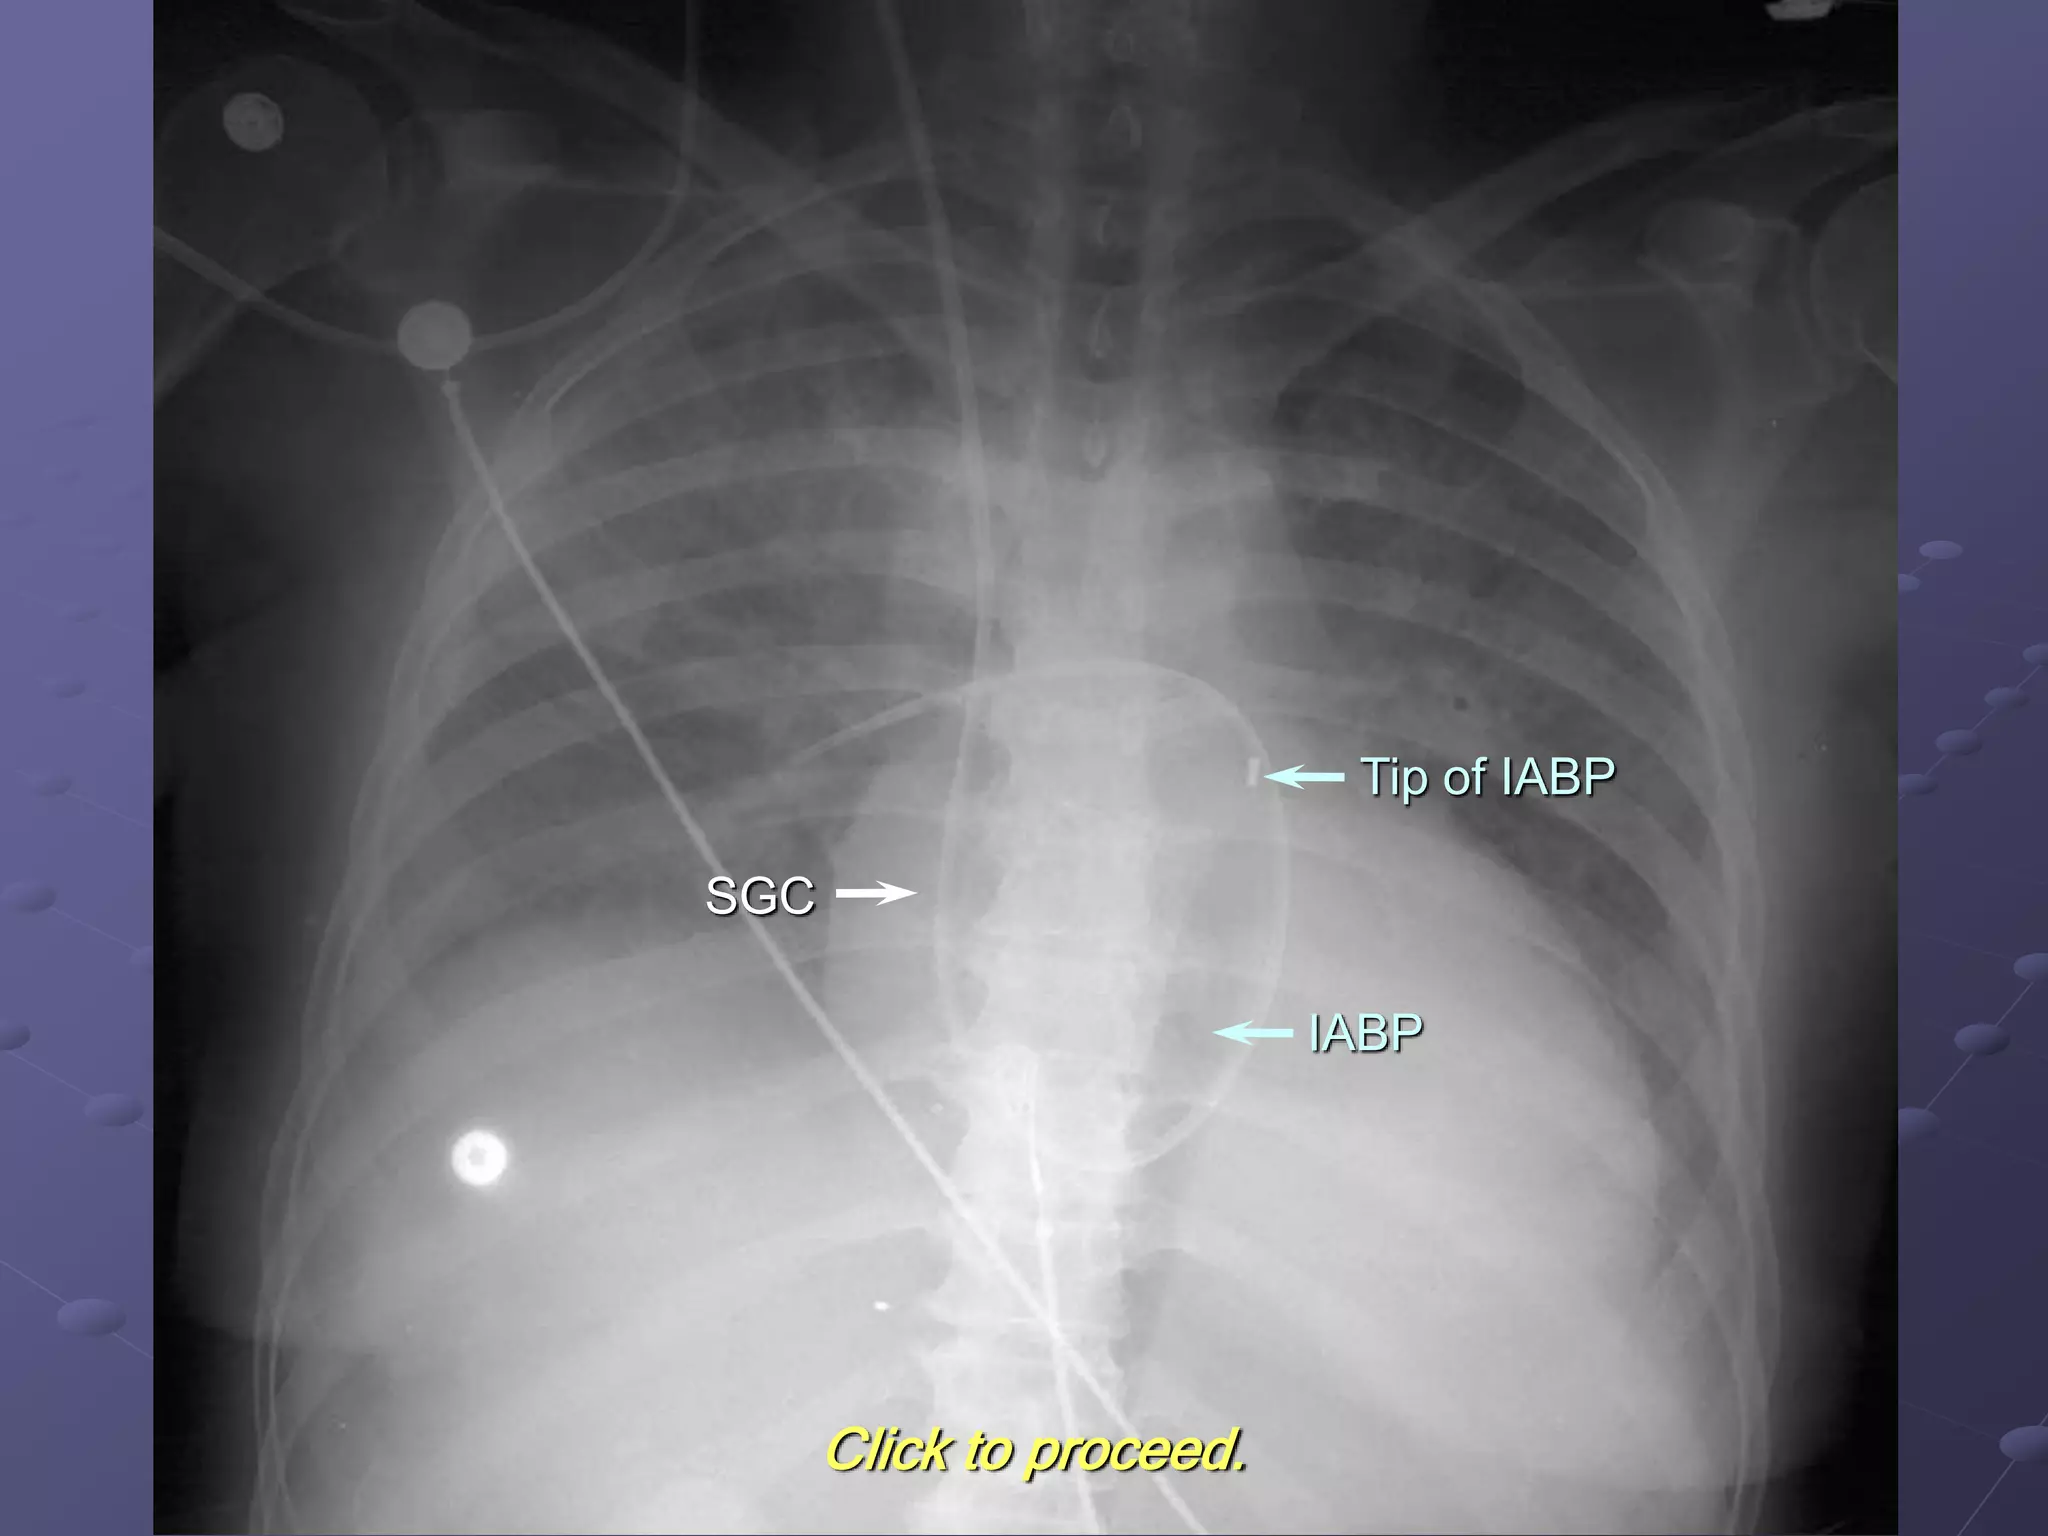

The following radiograph demonstrates an IABP in the proper position.

Click to locate the SGC.

Click to locate the IABP tip.

SGC

Tip of IABP

Click to locate the IABP proper.

IABP

Click to proceed.